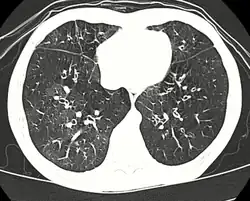

High resolution CT scan showing bronchiolitis obliterans with mosaic attenuation, bronchiectasis, air trapping and bronchial thickening[3]

Early in the disease chest radiography is typically normal but may show hyperinflation.[6] As the disease progresses a reticular pattern with thickening of airway walls may be present.[4][6] HRCT can also show air trapping when the person being scanned breathes out completely; it can also show thickening in the airway and haziness in the lungs.[11] A common finding on HRCT is patchy areas of decreased lung density, signifying reduced vascular caliber and air trapping. This pattern is often described as a "mosaic pattern", and may indicate bronchiolitis obliterans.[6]